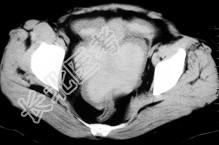

- 单项选择题女,32岁, 因停经46天,突发腹痛1天入院, 后穹隆穿刺抽出不凝血,CT检查如图所示, 下列说法错误的是 ( )

A、在左附件区可见一椭圆形略高密度病灶

B、病灶外缘较光整

C、盆腔内较高密度积液

D、此为宫外孕

E、此为卵巢巧克力囊肿